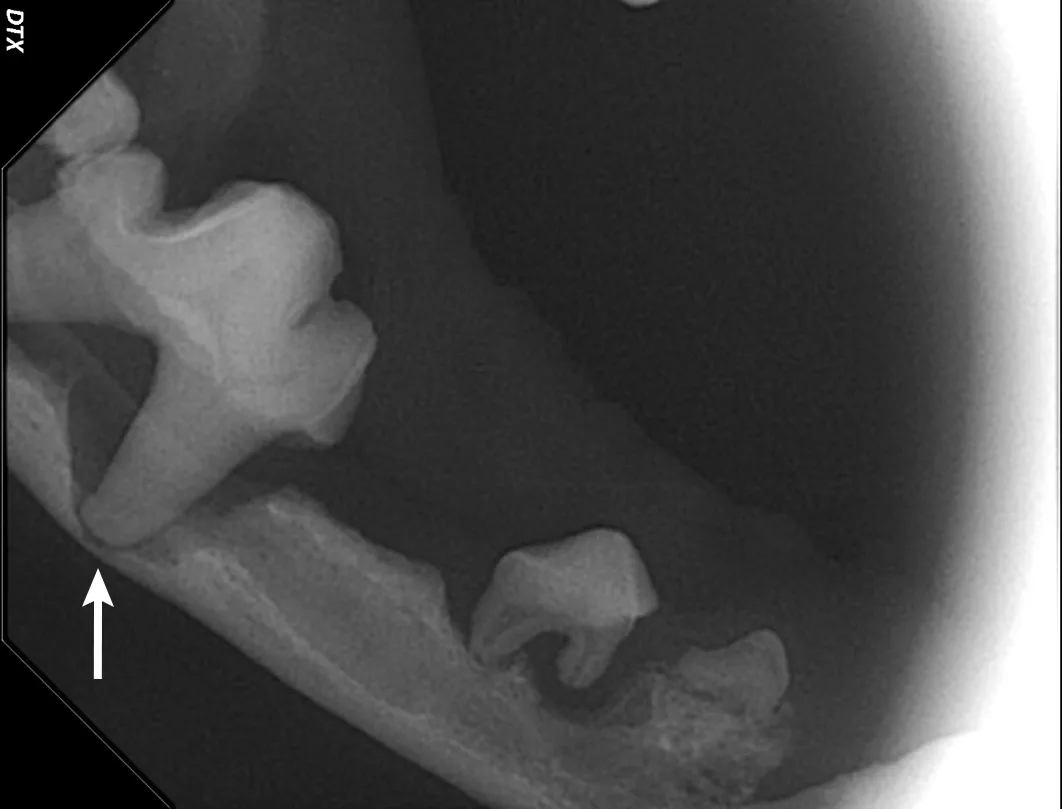

Iatrogenic fracture of the jaw can be a serious complication of surgical extractions and is most commonly associated with surgical extraction of mandibular canine teeth in dogs and cats and mandibular first molar teeth in dogs (Figure 10). These extractions can be difficult to perform, as the root apexes are often located in close proximity to the ventral cortex of the mandible, possibly leading to significant bone loss when severe disease is present and increasing the risk for iatrogenic fracture (Figure 11).

Pathologic fracture (arrow) secondary to severe periodontal disease of the right mandibular first molar tooth in a dog

Severe periodontal disease affecting the right mandibular first molar tooth in a dog. Careful extraction technique is necessary to extract the tooth without creating an iatrogenic fracture.

Preoperative intraoral radiographs are critical for assessing fracture risk, especially prior to surgical tooth extraction, and can be used to modify the procedure or refer a patient with high fracture risk to a board-certified veterinary dentist.